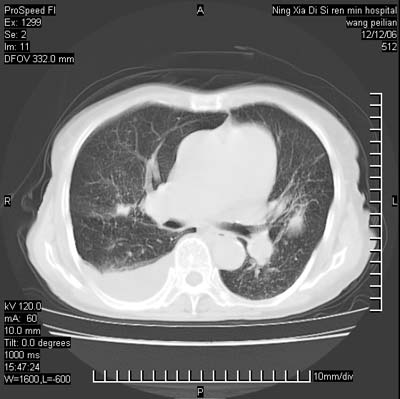

标题: CT5609:胸部:女77 病史不详 [打印本页]

标题: CT5609:胸部:女77 病史不详

两肺可见多个大小不等的结节,左侧有胸水,纵隔淋巴结增大,考虑是细支气管肺泡癌

两肺尖纤维索状影,两下肺结节块状影,且有钙化灶,右胸腔积液。考虑肺结核并胸膜炎。

双侧肺结核伴右侧胸腔积液.

两肺尖纤维索状影,两下肺结节块状影,且有钙化灶,右胸腔积液。考虑肺结核并胸膜炎肺间质纤维化

考虑:1、慢性支气管炎合并全小叶型肺气肿、间质纤维化;

2、双肺结核;

3、右侧胸膜炎(积液)。

1、双肺继发型肺结核(以纤维、增殖灶为主);

2、右侧胸腔积液;

3、其余符合老年肺改变。

双肺见多个结节状及条索状影,双侧胸腔积液,右侧叶间积液,考虑结核性胸膜炎